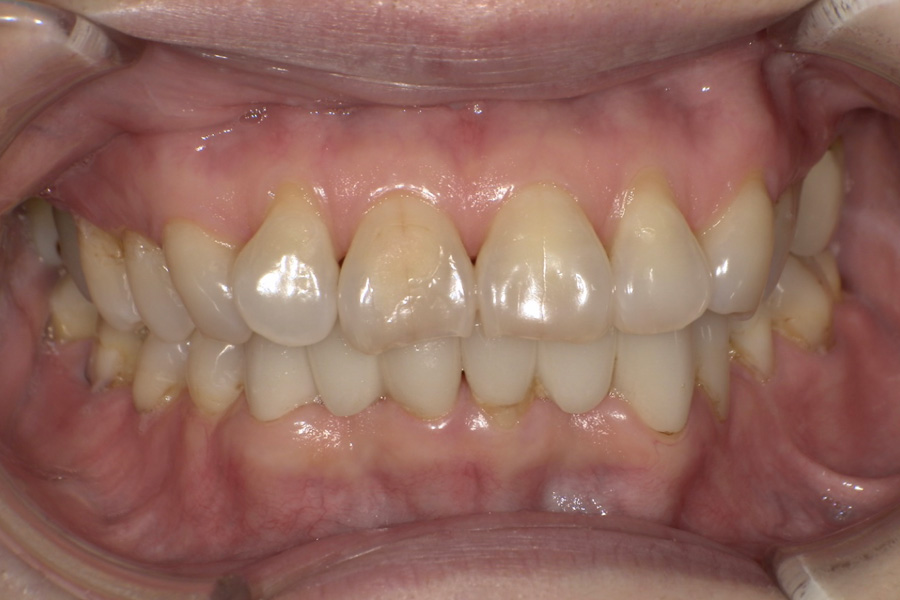

虫歯があるから削ったり悪くなったから抜くのではなく、まずは虫歯と歯周病が起きないようにより良い環境づくりをすること、そうすることによって歯を長く維持することが可能となります。

そのためには、健康状態に関する情報と生活習慣などの状況を把握したうえで、お口の中のリスク評価をおこないます。

その結果をもとに、お一人お一人にあった治療計画をご提案させていただきます。